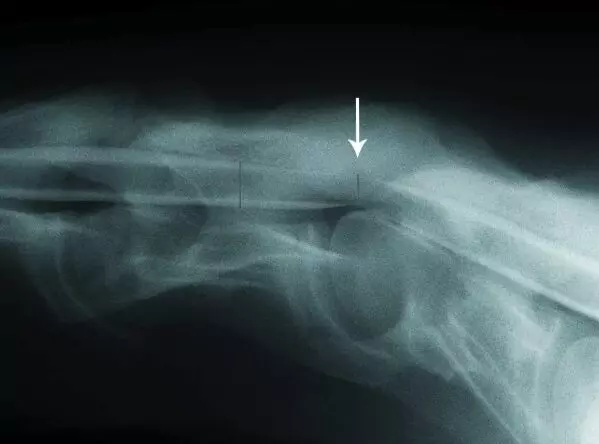

- Radiographs (X-rays): Show misaligned vertebrae or narrowing of the spinal canal.

- Myelogram: Injects dye into the spinal fluid to highlight any impingement on the spinal cord.

- Magnetic resonance imaging (MRI) provides high-resolution images of the horse’s spinal cord, which is particularly useful in borderline cases.